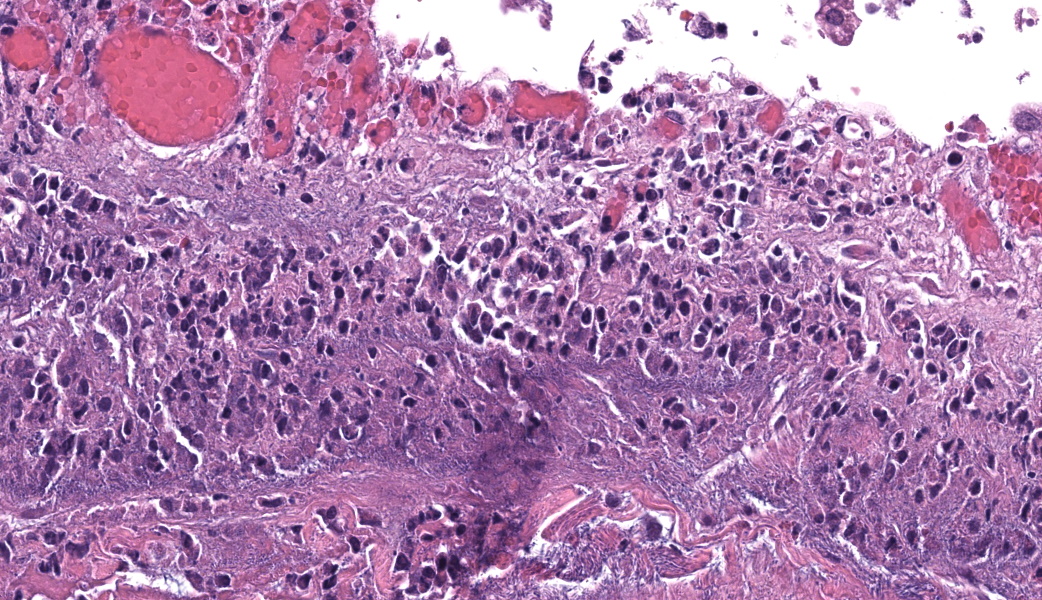

- aeruginosa ISH of liver: bacteria strongly positive, located diffusely within sinusoids and concentrated around vessels (Fig. 3 & 4).

Gram stain: Gram-negative rod-shaped bacteria associated with areas of inflammation and necrosis in the liver and gallbladder and presence of Gram-negative bacteria in circulation in the glomeruli and pulmonary vasculature.

Microscopic Description:

Gallbladder and liver: The gallbladder and adjacent portal tracts are effaced by multifocal to coalescing areas of coagulative and lytic necrosis admixed with foci of suppurative inflammation. The gallbladder is transmurally severely expanded by numerous neutrophils, scattered lymphocytes and histiocytes, abundant polymerized fibrin, necrotic debris eosinophilic proteinaceous fluid (edema), extravasated red blood cells (hemorrhage), and mats of extracellular rod-shaped bacteria (bacilli). Multifocally, blood vessels in the gallbladder are distorted by endothelial and/or mural necrosis and innumerable bacilli. Some vessels are partially occluded by fibrin and bacterial thrombi. Remaining intact vessels are congested. There is marked loss of gallbladder epithelium characterized by hypereosinophilia and loss of nuclear detail (necrosis), occasionally seen sloughing into the lumen admixed with neutrophils, fibrin, and red blood cells. Throughout the liver, bile ducts and portal vasculature undergo similar changes of varying severity (Fig 2). Bacilli are located extracellularly within portal areas and within sinusoids or intracellularly within macrophages. There are moderate, acute, multifocal loss of hepatocellular detail admixed with areas of fragmented chromatin and karyolytic debris (coagulative and lytic necrosis). Remaining hepatocytes are mildly to moderately swollen by small to medium-sized, round, clear, cytoplasmic vacuoles.